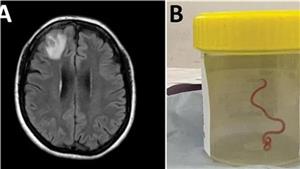

دودة حية